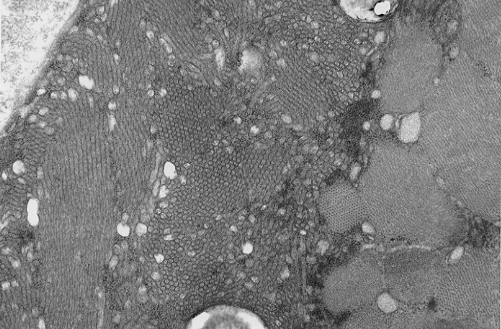

Pathology of the case: On hematoxylin-eosin stained frozen sections, there are many stongly basophilic, irregular subsarcolemmal depositions (Panel A and B). There is no significant variation in fiber diameter, increase in centrally located nucleus, inflammation, necrotic fiber, regenerating fibers or target fibers. These deposits appear bright red on modified Gomori's trichrome (Panel C). On ATPase reaction at pH 4.6 (dark fibers are type 1, pale fibers are type 2a while intermediate-intensity fibers are type 2b), there is no fiber type predominance (Panel D). Although the deposits are not visualized in the ATPase preparation, they are strongly reactive in NADH-TR reaction. Intesestingly, these deposits are not visualized in another preparation of oxidative enzyme- succinate dehydrogenase (Panel F). On the adenylate deaminase preparation, these deposits are strongly reactive (Panel G). The subsarcolemmal deposits are well visualized under the electron microscope which is electron dense (Panel H). On cross sections, these deposits are bundles of densely packed polygonal to round tubules with double walls that are arranged in small fascicles (Panel  I and J). The tubules are about 50-80 nm in diameter. The tubular aggregates also arrange in longitudinal bundles that run along the myofibrils (Panel K).

On resin embedded semithin sections, tubular aggregates may measure over 40 mm in length on longitudinal sections. At the ultrastructural level, tubular aggregates appear as masses of bundles of long, straight, parallel tubules in between myofibrils especially beneath subsarcolemmal locations. They are often double barrel and contains an inner tube but they may be up to eight inner tubes. The outer tube is usually about 50 nm in diameter but may be as large as 80 nm. The inner tubules are 20-30 nm in diameter.

In a study of muscle fibers from affected members of a family with a dominantly inherited tubular aggregate myopathy showed that the presence of tubular aggregates potentiated the calcium loading capacity of slow muscle fibers, when compared with control individuals. Tubular aggregates were functional equivalents to hypertrophy of the terminal cisterns of the sarcoplasmic reticulum and represented  an adaptive response to an increased calcium influx. In electron microscopy, there are suggestive connections between tubular aggregates and lateral cisternae of sarcoplasmic reticulum 5,6,7. Dilated sacs of sarcoplasmic reticulum may be associated with the aggregates.